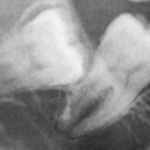

L'avulsione dei terzi molari inferiori inclusi rappresenta una componente fondamentale dell'attività clinica del chirurgo orale. La lesione del nervo alveolare inferiore è in assoluto...

Coronectomia: alternativa all’estrazione dei denti denti del giudizio inferiori